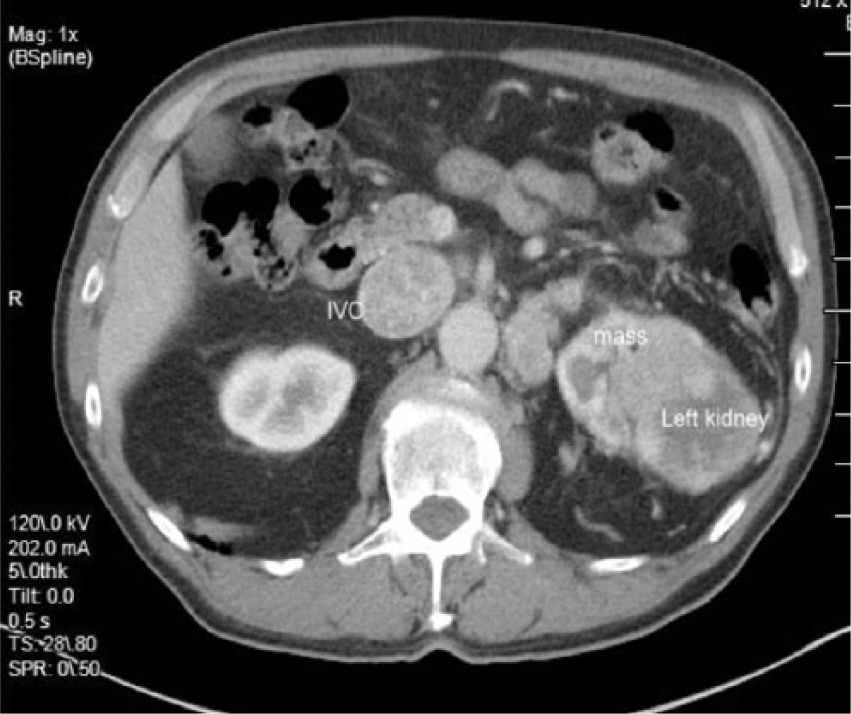

Cross-sectional computed tomography image showing the thrombus in the inferior vena cava (IVC) and the mass on left kidney.

An elderly man in his early seventies was referred to the hospital as an outpatient to undergo an abdominal aortic aneurysm (AAA) screening. The patient had a history of smoking for 20 years. The sonographic examination was performed on an Acuson 2000 ultrasound system (Siemens, Washington, DC), with a curved array C5-2 probe (2-5 MHZ bandwidth). Sonographic findings showed no evidence of an AAA. Velocities and Doppler waveforms throughout the abdominal aorta were normal and showed no significant stenosis. During the examination, the sonographer observed echogenic material in the area of the inferior vena cava (IVC). Upon further examination, the IVC appeared to be thrombosed (Figures 1 and 2). Color Doppler imaging was used to confirm that the IVC was partially obstructed (Figure 3). A transverse view of the IVC and aorta also showed a thrombus in the left renal vein (Figure 4). This prompted the sonographer to extend the examination to the left kidney where a partially exophytic mass located on the anterior/superior portion of the left kidney was seen (Figures 5 and 6). The mass measured 5.43 cm long, 5.31 cm wide, and 4.30 cm anterior-posterior (AP) dimension. Color Doppler imaging showed significant vascularity within the mass (Figure 6). The findings were suspicious for renal cell carcinoma, and the patient shortly thereafter had additional testing with a computed tomography (CT) scan of the abdomen and pelvis with contrast. The CT scan confirmed a mass in the left kidney with direct tumor extension into the left renal vein. A thrombus was seen in the IVC both above and below the level of the renal veins. However, it could not be determined by imaging if the thrombus was related to bland thrombus rather than tumor thrombus. Also noted in the CT findings were prominent venous collaterals in the retroperitoneal region centrally and on the left. The patient had a complete left nephrectomy, and the placement of an IVC filter was also performed. The pathology report confirmed a 6.0 cm multifocal renal cell carcinoma with a large tumor extension into the left renal vein. The tissue histology using a hematoxylin and eosin stain showed a Fuhrman Grade 3 tumor, and the cancer was noted to be of a conventional clear cell type, which is the most common.